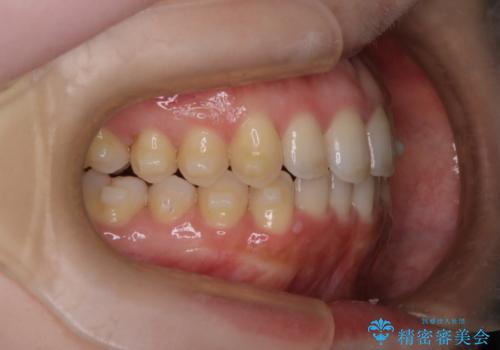

【インビザライン】オープンバイトを治したい

- 前歯の凸凹を主訴に来院された患者様です

骨格性の下顎前突傾向もあったため、臼歯関係の遠心移動も行うことで綺麗な仕上がりで矯正を終了することができました。

遠心移動を行うことで期間はかかりましたが、良い状態で仕上がっています。